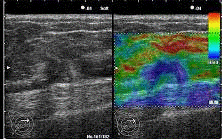

нажатия на экран ультразвукового сканера. На рисунке 8 по центру в виде зелёной

прерывистой линии отображается данный параметр и он находится в норме.

Что касается рисунка 9,

то здесь сила нажатия неверная и в эластограмме получается изображение с

значительными артефактами. Цветовая шкала жесткости представлена в верхнем

левом углу. Обычно, Soft (красный цвет) - соответствует более мягким тканям,

Нard (синий цвет) - более жестким тканям, а сама эластограмма строится в окне

справа (зоне интереса), но у каждой компании-производителя это реализуется

по-своему. На данном ультразвуковом изображении (рис. 8) видно, что в обычном

В-режиме имеется некое включение, а в режиме эластографии совершенно четко

видно, что оно твердое и вероятно злокачественное.

Рис. 8. Метод

компрессионной эластографии (оптимальная сила нажатия на датчик)

Рис. 9. Метод

компрессионной эластографии (неправильная сила нажатия на датчик)